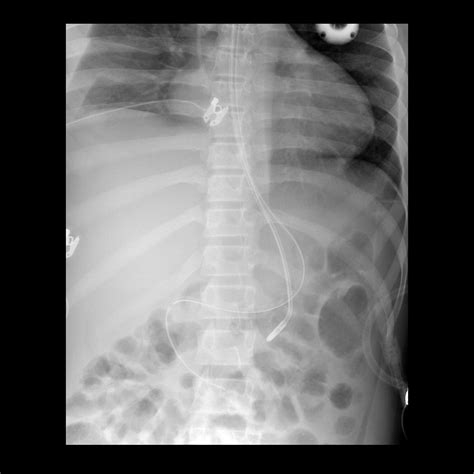

• Radiographic Imaging: An X-ray is the most definitive method to confirm the tip of the tube is in the stomach or duodenum.

5. Verification Aspirate gastric content or use an X-ray to confirm placement. Prevents accidental pulmonary entry.